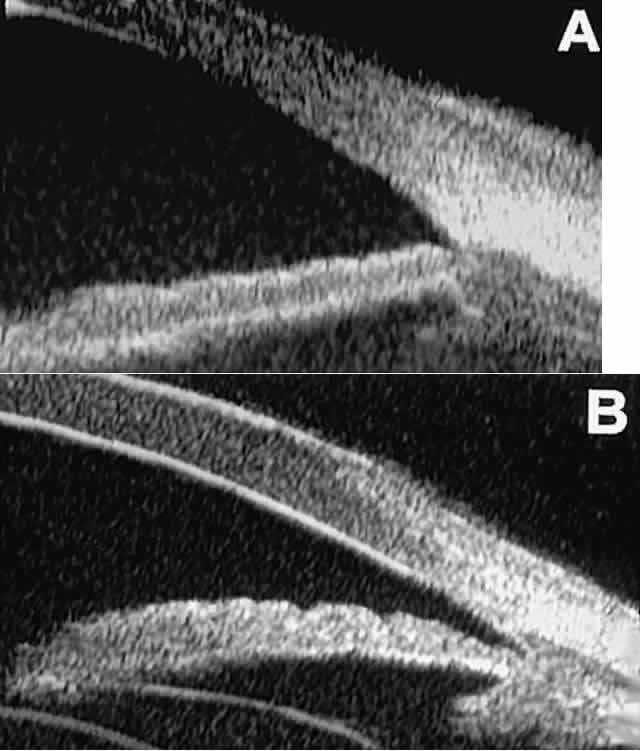

The role of UBM in the preoperative assessment of eyes with cataract is as yet unknown. In certain eyes, however, UBM may reveal features or abnormalities that could alter the ophthalmologist's surgical approach. Postoperatively, UBM can show the size and location of an intraocular lens (IOL) and the positioning of the haptics. A posterior chamber IOL appears on UBM as a highly reflective plate (corresponding to the lens optic) in the retropupillary plane with reverberation artifacts behind it (Fig. 17A). In contrast, an anterior chamber IOL appears on UBM as a sonoreflective plate located anterior to the pupillary plane (see Fig. 17B). In most eyes with a posterior chamber IOL, UBM can show whether the haptics are in the capsular bag (Fig. 18A), in the ciliary sulcus (see Fig. 18B), or in some other anatomic location12 (e.g., resting on the peripheral iris or secured with sutures to the sclera). The haptics are easier to locate if they are made of polymethyl-methacrylate than if they are made of proline because the former has a stronger reflectance.

Fig. 18 . Localization of posterior chamber IOL haptics by UBM. A. Haptic in capsular bag (arrow). B. Haptic (bright object just behind peripheral iris) in iridociliary sulcus.